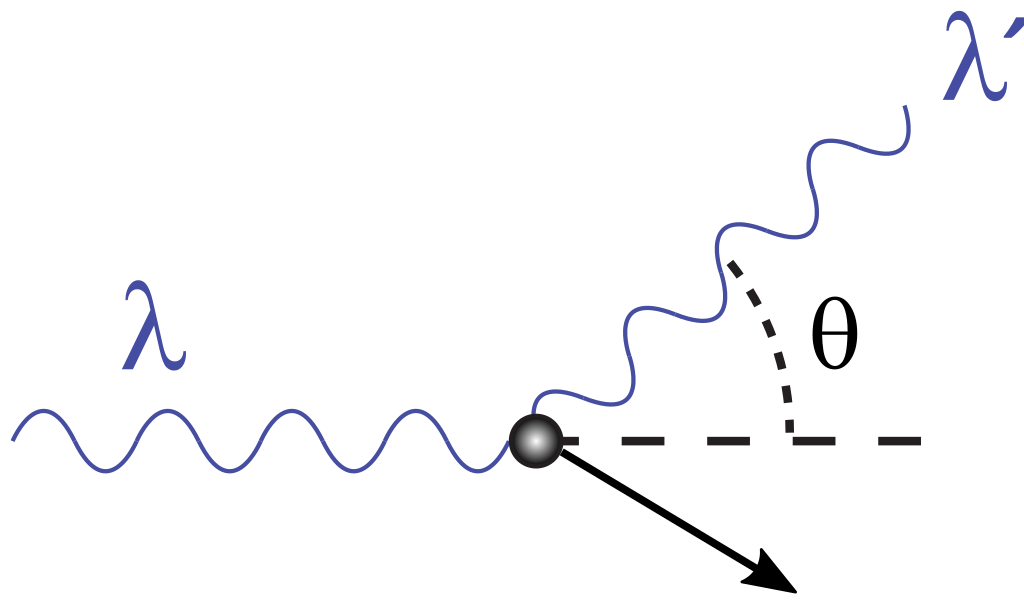

Дело в том, что тело человека — не вакуум. Эти гамма-фотоны, прежде чем долететь до детектора, ныряют в ткани, сталкиваются с атомами... Это называется комптоновское рассеяние.

В итоге детектор ловит кучу фотонов, которые сбились с пути, потеряли часть энергии и летят не туда, куда должны. Это — мусорные события. Шум. Он забивает полезный сигнал, делает картинку нечёткой, и в итоге врач может увидеть не чёткую опухоль, а какое-то невнятное пятно.

Чтобы с этим бороться, учёные просто фильтруют эти мусорные сигналы и выбрасывают их. Типа: «нет сигнала — нет проблемы». Но что, если этот мусор на самом деле — не мусор?

Группа учёных из МФТИ и Института ядерных исследований РАН решила проверить эту аксиому на своей уникальной установке. Они взяли пары запутанных гамма-фотонов, рождённых при аннигиляции (как в реальном ПЭТ), и начали их намеренно расшвыривать под разными углами — моделировали то самое комптоновское рассеяние, которое и портит картинку в томографе.